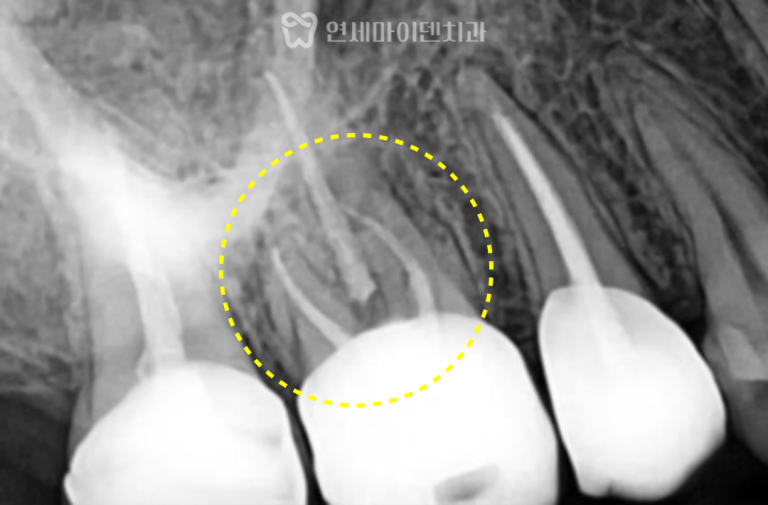

파노라마 사진을 통해 확인한 결과,

- 6번 치아 부위의 공간이 심하게 좁아져 있었으며

- 위아래 사랑니는 모두 자라 있었고, 일부는 충치가 심했습니다.

특히 오른쪽 아래 사랑니(8번)는

앞 어금니를 제자리로 되돌리는 데 방해가 되어,

공간 확보를 위해 사랑니 발치 후

부분교정 치료를 진행하기로 하였습니다.